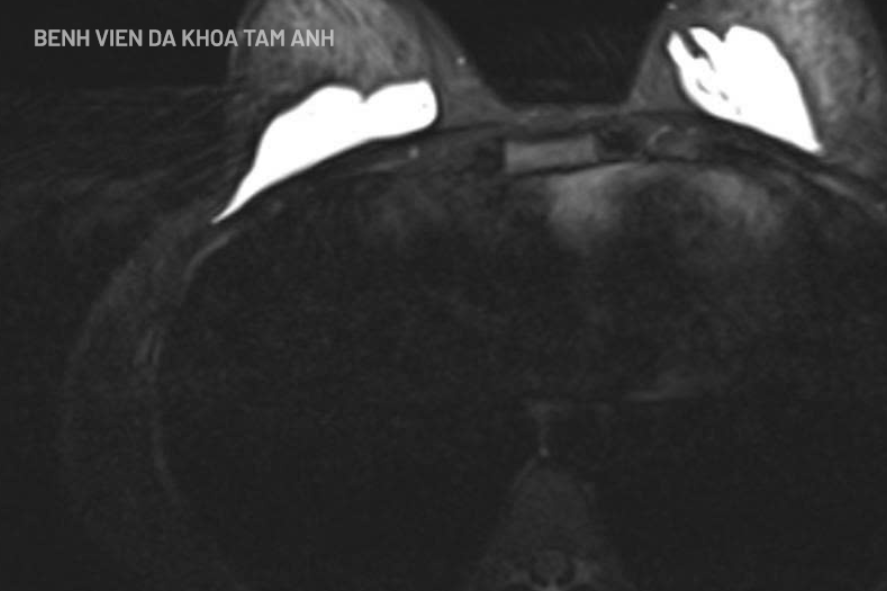

Thăm khám ban đầu, chị Lê không có dấu hiệu viêm cấp song có nhiều sẩn cục dưới da tuyến vú và vùng mông. Khi chụp MRI ngực ghi nhận hình ảnh chất làm đầy khu trú phía sau nhu mô tuyến vú và trước cơ ngực lớn. Siêu âm vùng mông cũng phát hiện các ổ dịch rải rác không đồng nhất dưới da.